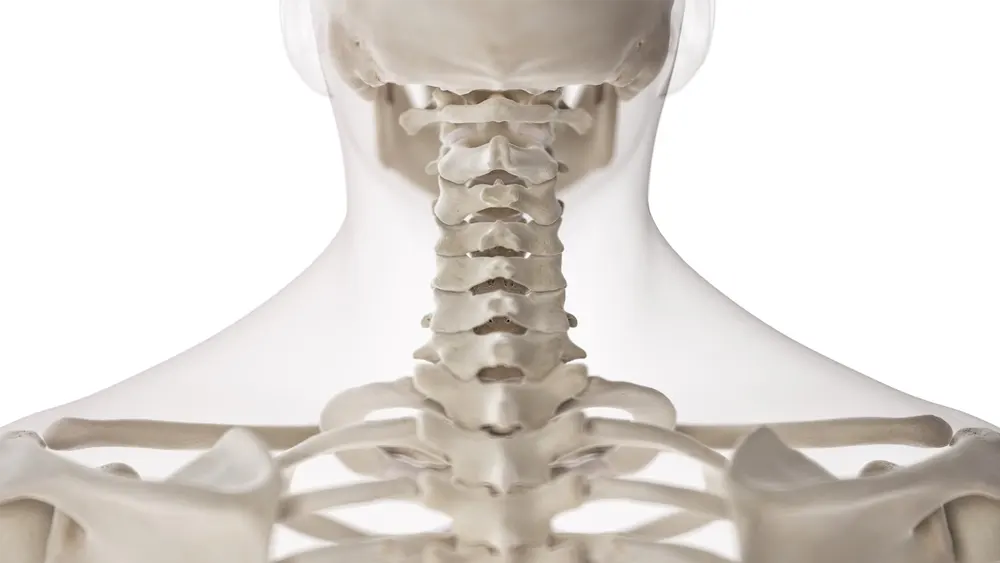

Understanding the Upper Cervical Spine

The upper cervical spine consists of the atlas (C1) and axis (C2), which sit directly beneath the skull. This region supports the head, protects the brainstem, and allows for a wide range of motion while maintaining stability. Because of its location, the upper cervical spine plays a direct role in posture, balance, and neurological communication between the brain and the rest of the body.

Even small misalignments at the craniocervical junction can influence how the rest of the spine compensates. When the head is not balanced over the body, muscular tension patterns, postural shifts, and neurological stress may develop gradually. Over time, these compensations can place strain on surrounding structures and contribute to symptoms far from the neck itself.

Upper cervical chiropractic care addresses this region specifically rather than applying generalized adjustments throughout the spine. By focusing on the foundation of head and neck alignment, we evaluate whether restoring balance at the top of the spine allows the rest of the body to function with less structural interference.